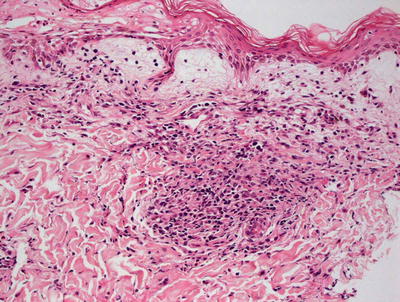

Fig. 11.1

A lymphocytic infiltrate is seen underneath a necrotic epidermis in toxic shock syndrome